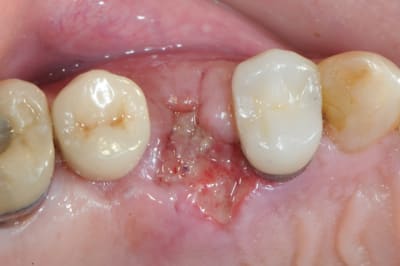

5-6- sutures du conjonctif pour obtenir l'étanchéité (enfin , on essaye)

7- résultat à j+7

c'est peut être un hasard, mais le patient est justement passé aujourd'hui. j'en ai bien sure profité pour faire une photo...

on est ici à j+5 mois, pas de perte osseuse vestibulaire.

la pose d'implant ( flapless très certainement) est prévue pour dans 15 jours.